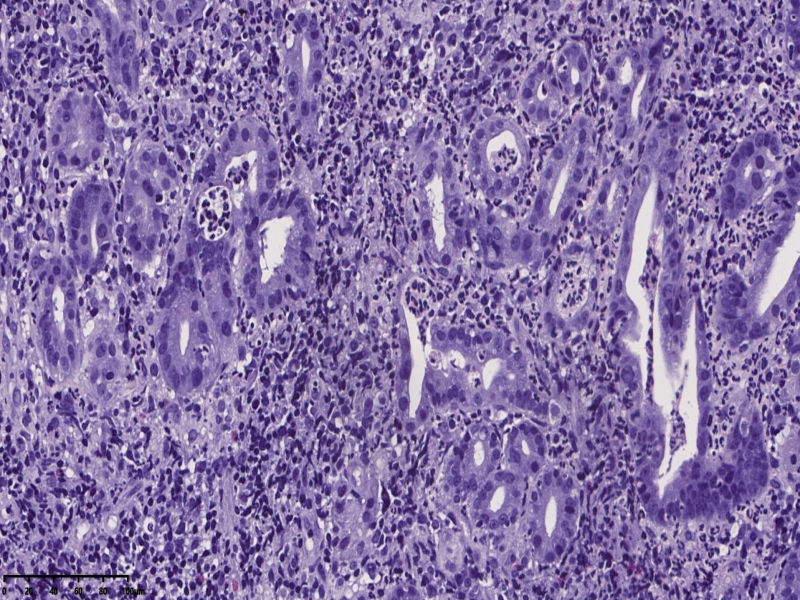

镜下,胃体型粘膜组织,炎症明显,有活动性炎,部分腺体形态不规则,呈角,上皮细胞单层,有异型,但是炎性反应性增生也不除外。

对比牵手癌还是有差距,不够诊断。254320

胃体:慢性胃炎,低级别上皮内瘤变,局灶腺体高级别上皮内瘤变伴畸形腺体(跳跃分

布),符合局灶黏膜内癌变(牵手癌);KI67:60%,CK7:部分+,CK20:表层腺体+,MUC5:

30%,MUC6:60%+,Villin5%,CDX-2 -,p53 60%,CEA 10%, SYN 散在+,10%;